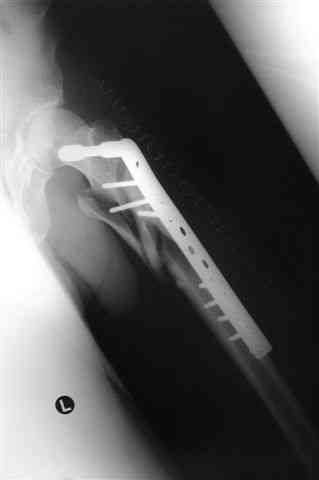

Бедро фиксировал длинной DCS.

По типу бриджинг плэйтин, крюком удалось низвести малый вертел и фиксировать винтом для восстановления медиальной стенки.

> Бедро фиксировал длинной DCS.

А почему не гвоздем закрыто?

> По типу бриджинг плэйтин, крюком удалось низвести малый вертел и фиксировать

IMHO это лишние трудозатраты, ничего плохого не случается при оставлении малого вертела в покое.

ET>> Бедро фиксировал длинной DCS.

AC>А почему не гвоздем закрыто?

Изначально планировался длинный гамма гвоздь , но набор заказывается обычно из Йоханнесбурга, а в этот раз все совпало с новогодними празднованиями и вся жизнь была *парализована* новогодней фиестой:-((, поэтому безуспешно прождав 3-4-5 дней обещанной доставки зафиксировал пластиной- жаль, что так всй случилось У местного